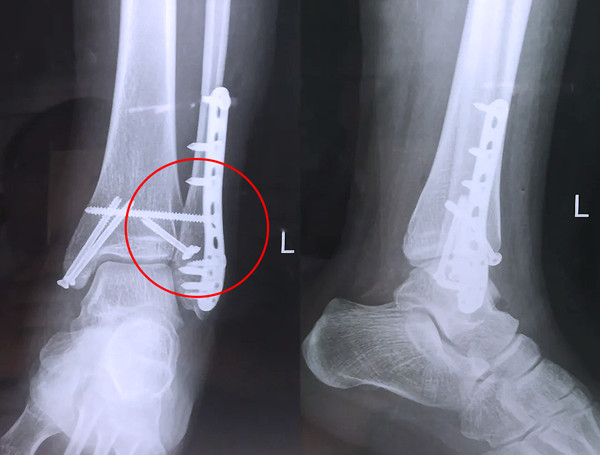

踝關(guān)節(jié)骨折在X影像上的表現(xiàn)有很多種。如內(nèi)踝骨折和外踝骨折,我們可以在影像上看到骨折處的骨折線是不連續(xù)的。還有后踝的骨折,內(nèi)踝、外踝、后踝聯(lián)合在一起發(fā)生的骨折,我們稱之為“三踝骨折”,這些都是在X影像上能夠顯示出來的。

三踝骨折